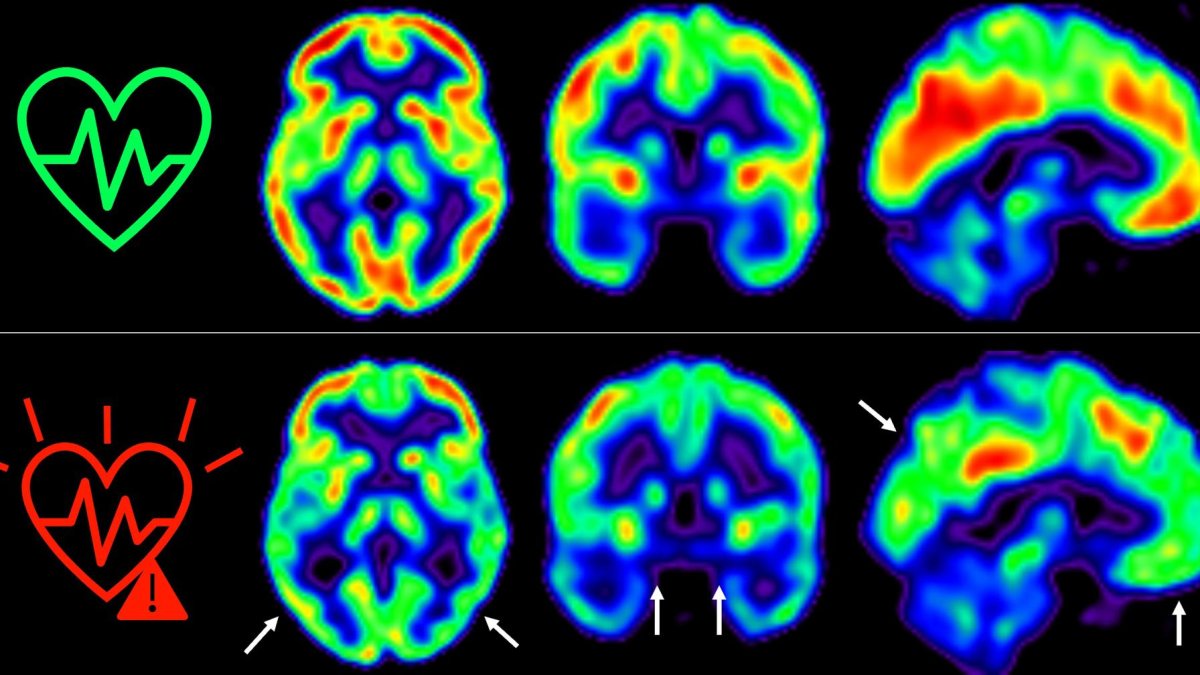

Las imágenes representan la captación de glucosa en el cerebro en individuos de mediana edad con bajo (arriba) o alto (abajo) riesgo cardiovascular sostenido 5 años.

Las personas de mediana edad con un riesgo cardiovascular elevado de forma sostenida durante cinco años experimentan -según el estudio- una mayor disminución del metabolismo cerebral medido a través de técnicas de imagen avanzadas.

Para la nueva investigación, el equipo siguió durante cinco años a los participantes de ese estudio. Aquellos que mantuvieron un riesgo cardiovascular elevado en ese tiempo sufrían “una disminución aún mayor del metabolismo cerebral”.

El declive metabólico cerebral era tres veces mayor que el de personas que se mantienen en bajo riesgo cardiovascular, destaca la primera firmante del artículo, Catarina Tristão-Pereira.